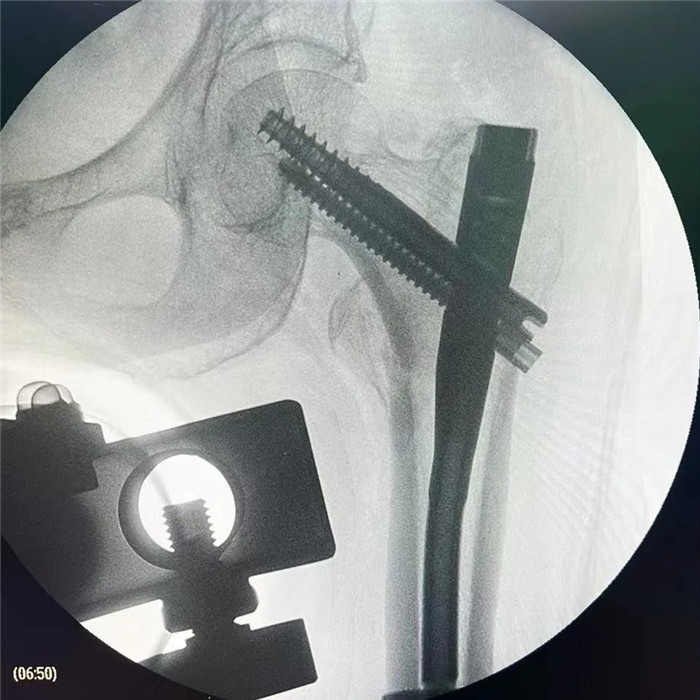

在手術(shù)團(tuán)隊(duì)及患者家屬的大力支持下,羅軍主任團(tuán)隊(duì)為洪阿婆實(shí)施了閉合復(fù)位INTERTAN內(nèi)固定術(shù)。雖然手術(shù)風(fēng)險(xiǎn)較大,但憑借精湛的技術(shù)及豐富的臨床經(jīng)驗(yàn),手術(shù)十分成功而且僅僅用了1個(gè)小時(shí),術(shù)中出血不多,術(shù)后患者恢復(fù)得很好,第二天就可以在起床活動(dòng),極大的提高了患者的生活質(zhì)量,避免了長期臥床造成的并發(fā)癥。